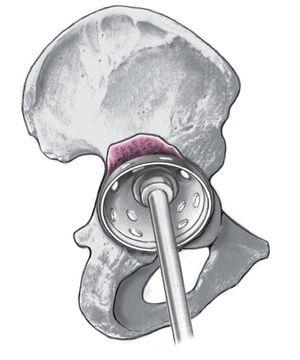

Figuras 12a a 12c. Fijación complementaria a través de la colocación de dos a tres tornillos de esponjosa en el hueso ilion (a). Colocación de los tornillos a ser posible en la dirección de las líneas de fuerza en la cadera (b, c).

Figura 13. Introducción del polietileno (a ser posible con los rebordes elevados); para obtener el mejor press-fit, es conveniente una ligera anterversión (5-10º) en la implantación. A continuación, cierre cuidadoso de la herida y colocación de un vendaje de compresión envolviendo toda la pierna y cadera.